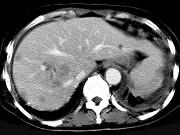

问题 男,42岁,中上腹痛,轻度黄疸,结合CT图像,提出最可能的诊断()

选项 A.肝脓肿 B.肝多发性囊肿 C.肝癌肝内转移伴门脉癌栓形成 D.胆管细胞癌 E.肝血管瘤

答案 C